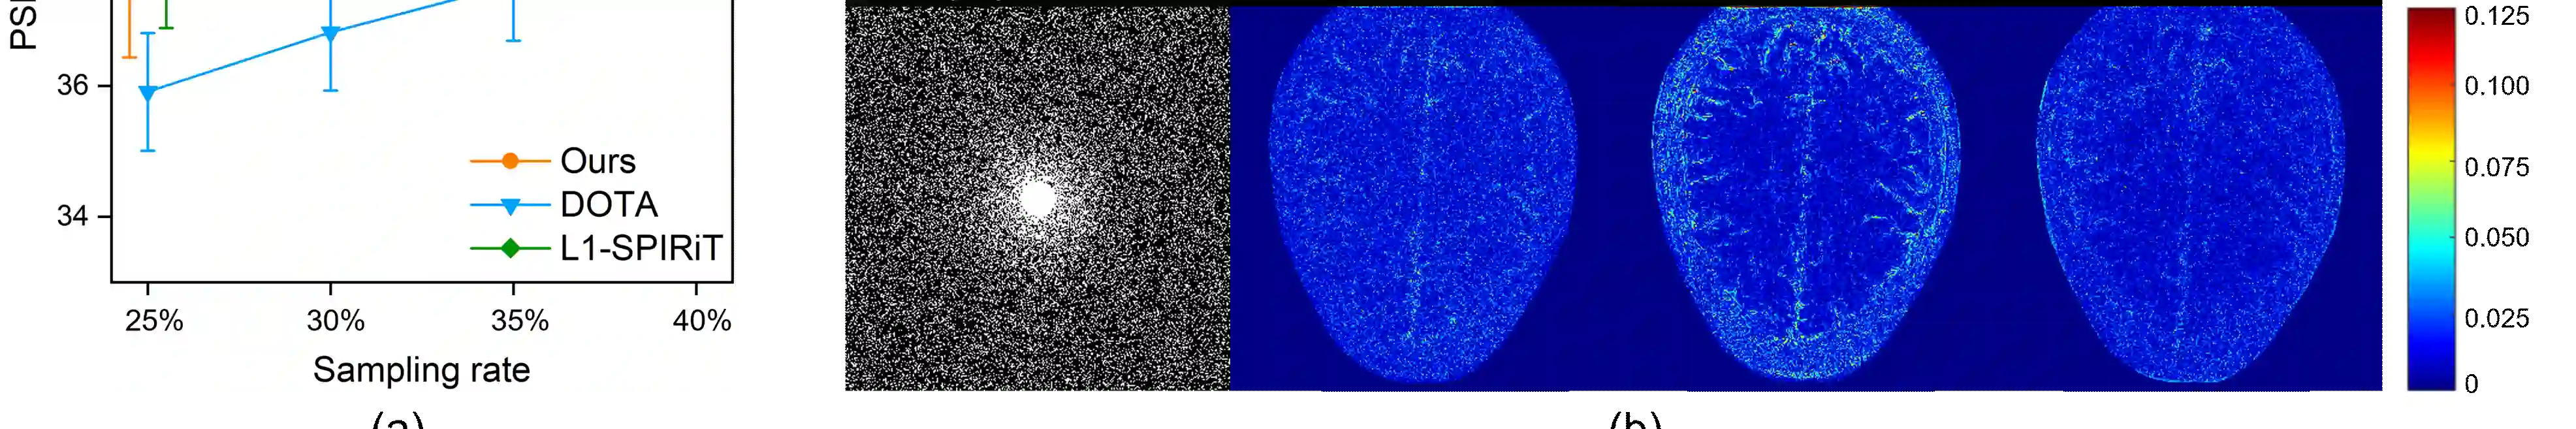

Magnetic resonance imaging (MRI) plays an important role in modern medical diagnostic but suffers from prolonged scan time. Current deep learning methods for undersampled MRI reconstruction exhibit good performance in image de-aliasing which can be tailored to the specific kspace undersampling scenario. But it is very troublesome to configure different deep networks when the sampling setting changes. In this work, we propose a deep plug-and-play method for undersampled MRI reconstruction, which effectively adapts to different sampling settings. Specifically, the image de-aliasing prior is first learned by a deep denoiser trained to remove general white Gaussian noise from synthetic data. Then the learned deep denoiser is plugged into an iterative algorithm for image reconstruction. Results on in vivo data demonstrate that the proposed method provides nice and robust accelerated image reconstruction performance under different undersampling patterns and sampling rates, both visually and quantitatively.